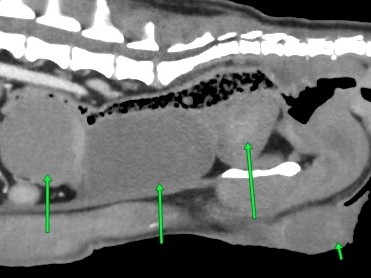

CT検査でわずかに見えていましたよね

ココにうっすら、

診えますか?

アップにしますと、診えてきましたね

一番右矢印が睾丸です